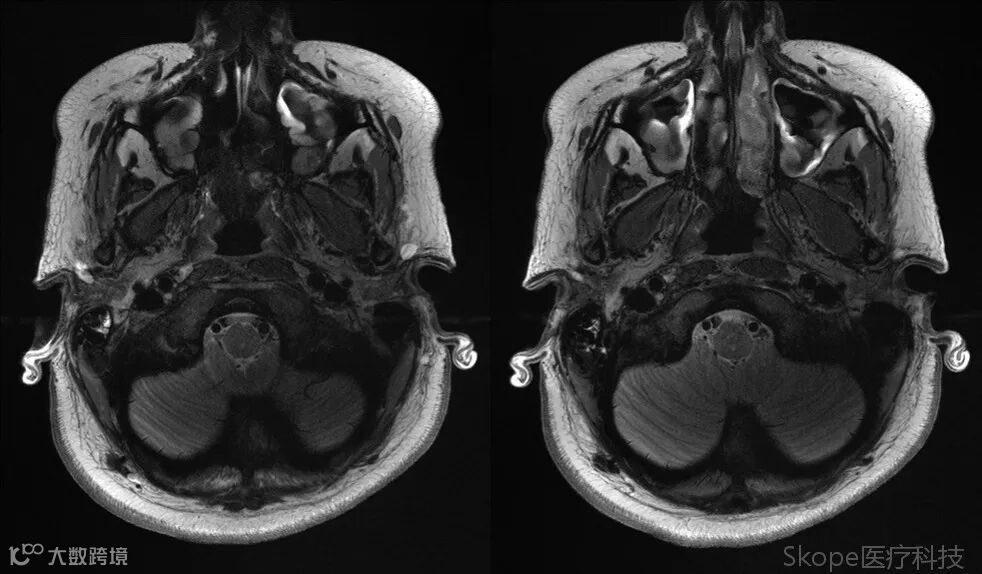

Axial T2 TSE

3D T2 Space FLAIR FS

采用高加速因子的同时,仍保持了高分辨率和高信噪比。